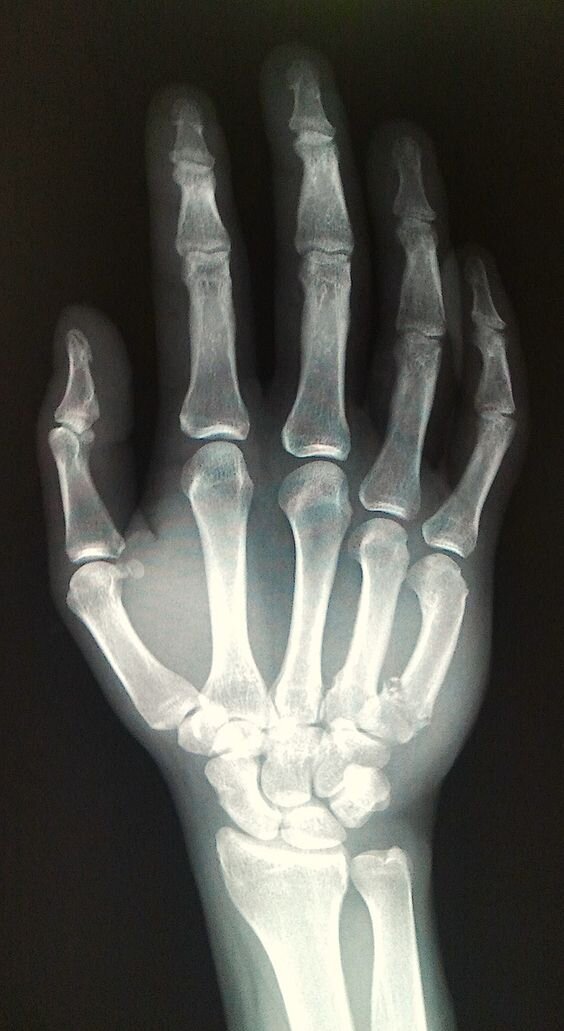

Рентген — это быстрая и безболезненная процедура, обычно используемая для получения изображений внутренней части тела.

Это очень эффективный способ изучения костей, который можно использовать для диагностики ряда заболеваний.

При прохождении через тело энергия рентгеновского излучения поглощается разными частями тела с разной скоростью. Детектор на другой стороне тела улавливает рентгеновские лучи после их прохождения и превращает их в изображение.

Плотные части тела, через которые рентгеновским лучам труднее проникнуть, например, кости, отображаются на изображении в виде простых белых областей. Мягкие части, через которые рентгеновские лучи могут легче проходить, такие как сердце и легкие, выглядят как более темные области.